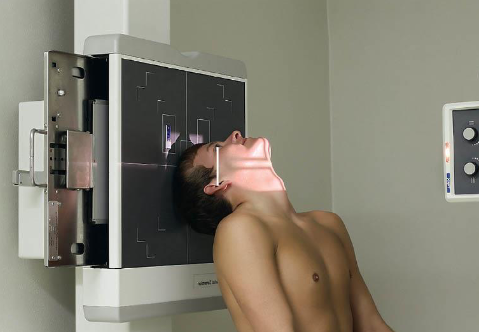

SMV (Schuller) skull

patient position:

upright (seated) or supine (torso elevated)

part position:

MSP centered to midline

MSP perpendicular to IR

IOML parallel with IR

patient hyperextends neck and rests head on vertex

respiration suspended

CR:

perpendicular through sella turcica and IOML

enters MSP of throat between angles of mandible (gonion)

passes through a point ¾ inch anterior to the level of the EAM